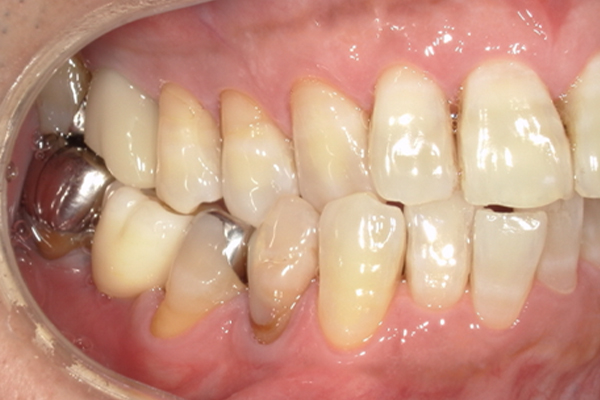

| 主訴 | 歯が痛い |

|---|---|

| 治療内容 | 右上奥歯に対するインプラント治療 (今後右下に対してもインプラント治療を予定) |

| 治療期間 | 6ヶ月 |

| 治療費 | 44万5千円 |

| 治療 リスク | インプラントを埋入したあと3ヶ月程度待ち時間が必要。 その期間は仮歯を使用していただきます。 |